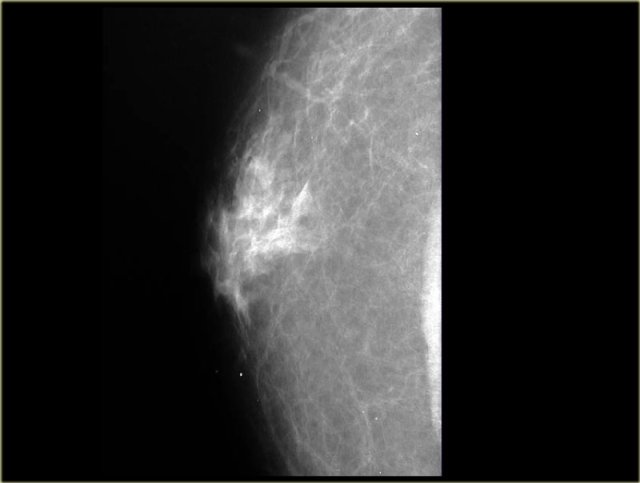

Dendritic pattern of gynecomastia Dendritic pattern of gynecomastia

Dendritic Pattern

The dendritic pattern is seen in the fibrotic or late phase.

There are dilated ducts, moderate epithelial proliferation and fibrosis.

On the left a mammogram showing a subareolar density with prominent extensions into the fat.

Usually the density is smaller than in the nodular pattern.

Classic benign chronic gynecomastia Classic benign chronic gynecomastia

On the mammogram on the left we can imagine, that there is fibrosis with extension into the fat.

This is different from the glandular edema-like appearance in the acute phase of gynecomastia.

The ultrasound shows a spiculated appearance.

These cases clearly demonstrate that gynecomastia can have an appearance which we would call malignant in a woman.

Unfortunately some of the malignant lesions in a man can look benign and we will show some examples in the next chapter.